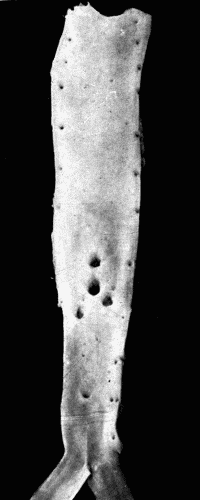

In the nodular form the lesions are found on the aorta and large branches particularly at or near the orifices of branching vessels. These nodules may increase in size, forming rather large, slightly raised plaques of yellowish-white color. They are, as a rule, irregularly scattered throughout the aorta and branches and tend to be more numerous and larger in the abdominal aorta. The initial lesion is in the media, consisting of an actual dissolution of this coat with rupture of the elastic fibers and infiltration with small round cells. There is thus a weak spot in the artery. Hypertrophy of the intimal cells takes place, layer upon layer being added in an attempt to strengthen the vessel at the injured place. Coincidently with this, there is thickening by a connective tissue growth in the adventitia. The process begins, at least in syphilis, around the terminals of the vasa vasorum. It will be recalled that the blood supply of the inner portion of the media comes[38] from within the vessel itself. As the intimal growth increases, the blood supply is cut off. The inevitable result is softening of the portion farthest from the lumen of the vessel. As a rule there has been a sufficient growth of connective tissue in the media and adventitia to repair the damage done to the media. This softening and dissolution gives rise to a granular debris composed of degenerated cells and fat. This is the so-called atheromatous abscess. There are no leucocytes as in ordinary pus. These "abscesses" are frequent and in rupturing leave open ulcers with smooth bases, the atheromatous ulcer. A further change which often takes place is calcification of the bases of the ulcers and calcification of the softened spots before rupture takes place. This only occurs in advanced cases. (See Fig. 3.)

Fig. 3.—Arteriosclerosis of the thoracic and abdominal aorta, showing irregular

nodules, atheromatous plaques, denudation of the intima, thin plates of bone scattered

throughout with spicules extending into the lumen of the vessel. Note the contraction

of the openings of the large branches, the rough appearance of the aorta and the greater

degree of sclerosis of the upper two-thirds, i. e., of the aorta above the diaphragm.

This aorta in the recent state was much thickened and almost inelastic. Fig. 3.—Arteriosclerosis of the thoracic and abdominal aorta, showing irregular nodules, atheromatous plaques, denudation of the intima, thin plates of bone scattered throughout with spicules extending into the lumen of the vessel. Note the contraction of the openings of the large branches, the rough appearance of the aorta and the greater degree of sclerosis of the upper two-thirds, i. e., of the aorta above the diaphragm. This aorta in the recent state was much thickened and almost inelastic.

Fig. 5.—Normal aorta. Compare with Fig. 3. Note the perfectly smooth, glossy appearance

of the intima. The openings of all the intercostal arteries are distinctly seen.

In the recent state this artery was highly elastic, capable of much stretching both

transversely and longitudinally. Fig. 5.—Normal aorta. Compare with Fig. 3. Note the perfectly smooth, glossy appearance of the intima. The openings of all the intercostal arteries are distinctly seen. In the recent state this artery was highly elastic, capable of much stretching both transversely and longitudinally.